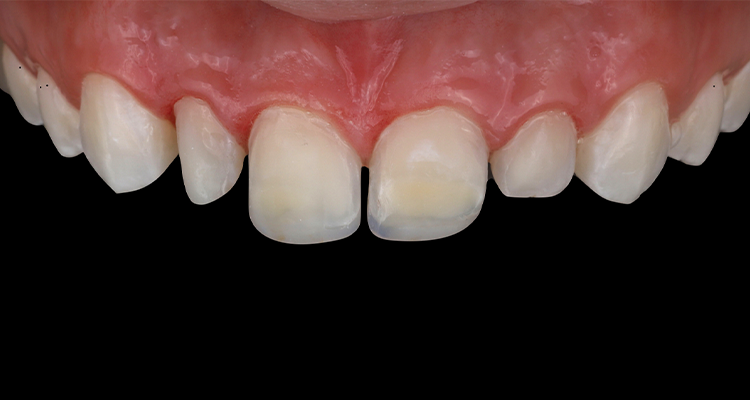

Durante a realização do exame intrabucal foram observadas restaurações do tipo facetas em resina composta nos dentes 12, 11, 21 e 22 com perda de brilho, formato insatisfatório e infiltrações.

1 | Aspecto inicial intrabucal com resina composta insatisfatória nos dentes 12, 11, 21 e 22.